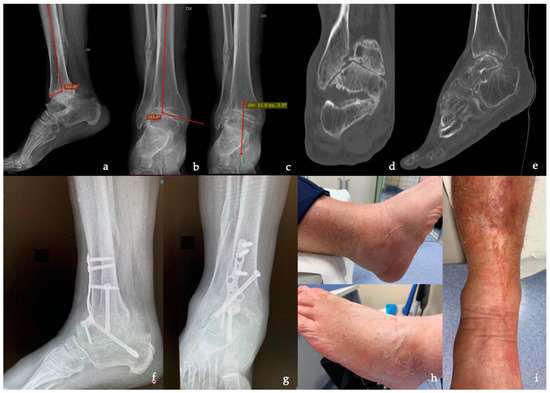

- Anterior distal tibial angle (ADTA), formed by the mechanical axis of the tibia and the TT joint orientation line in the sagittal plane (normal value: 80° ± 3°) [41];

- Coronal (or frontal) tibiotalar angle (CTTA), the superomedial angle between the longitudinal axis of the tibia, created by connecting two points in the middle of the proximal and the distal tibial shaft and the axis of the talus, defined by a line drawn through the talar shoulders in the anteroom-posterior view (normal value: 88.7° ± 5.1°) [42];

- Hindfoot alignment angle (HAA), formed by the intersection of the longitudinal axis of the tibial shaft and the axis of the calcaneal tuberosity (normal value: 5.6° ± 5.4°) [43].

| ADTA | 83.0° ± 12.0° (71–102) † | 77.8° ± 4.8° (65–82) ‡ | - |

| TTA | 23° ± 9.0° (17–38) † | 8 ± 2 (5–12) ‡ | - |

| CTTA | 97.5° ± 7° (90–108) † | 89.3° ± 2° (87–92) ‡ | - |

| HAA | 20° ± 5° (14–29) † | 9° ± 5° (5–13) ‡ | - |